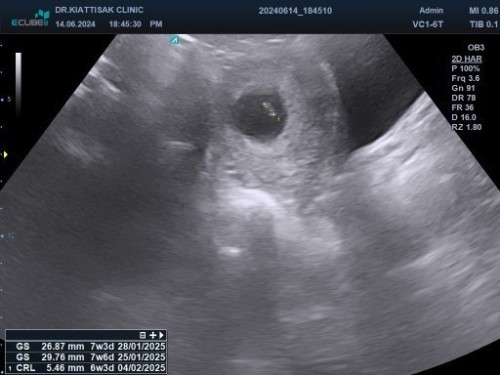

7 สัปดาห์ 3วันไม่พบหัวใจปกติไหมค่ะ

7 สัปดาห์ 3วันไม่พบหัวใจปกติไหมค่ะ และดูผลซาวด์เป็นยังไงบ้างค่ะ

12 วีคค่อยไปตรวจซ้ำอีกทีค่ะ ช่วงนี้กินโฟลิคไปก่อนนะคะ

อีก2สัปดาห์ไปซาวด์ใหม่จ้า